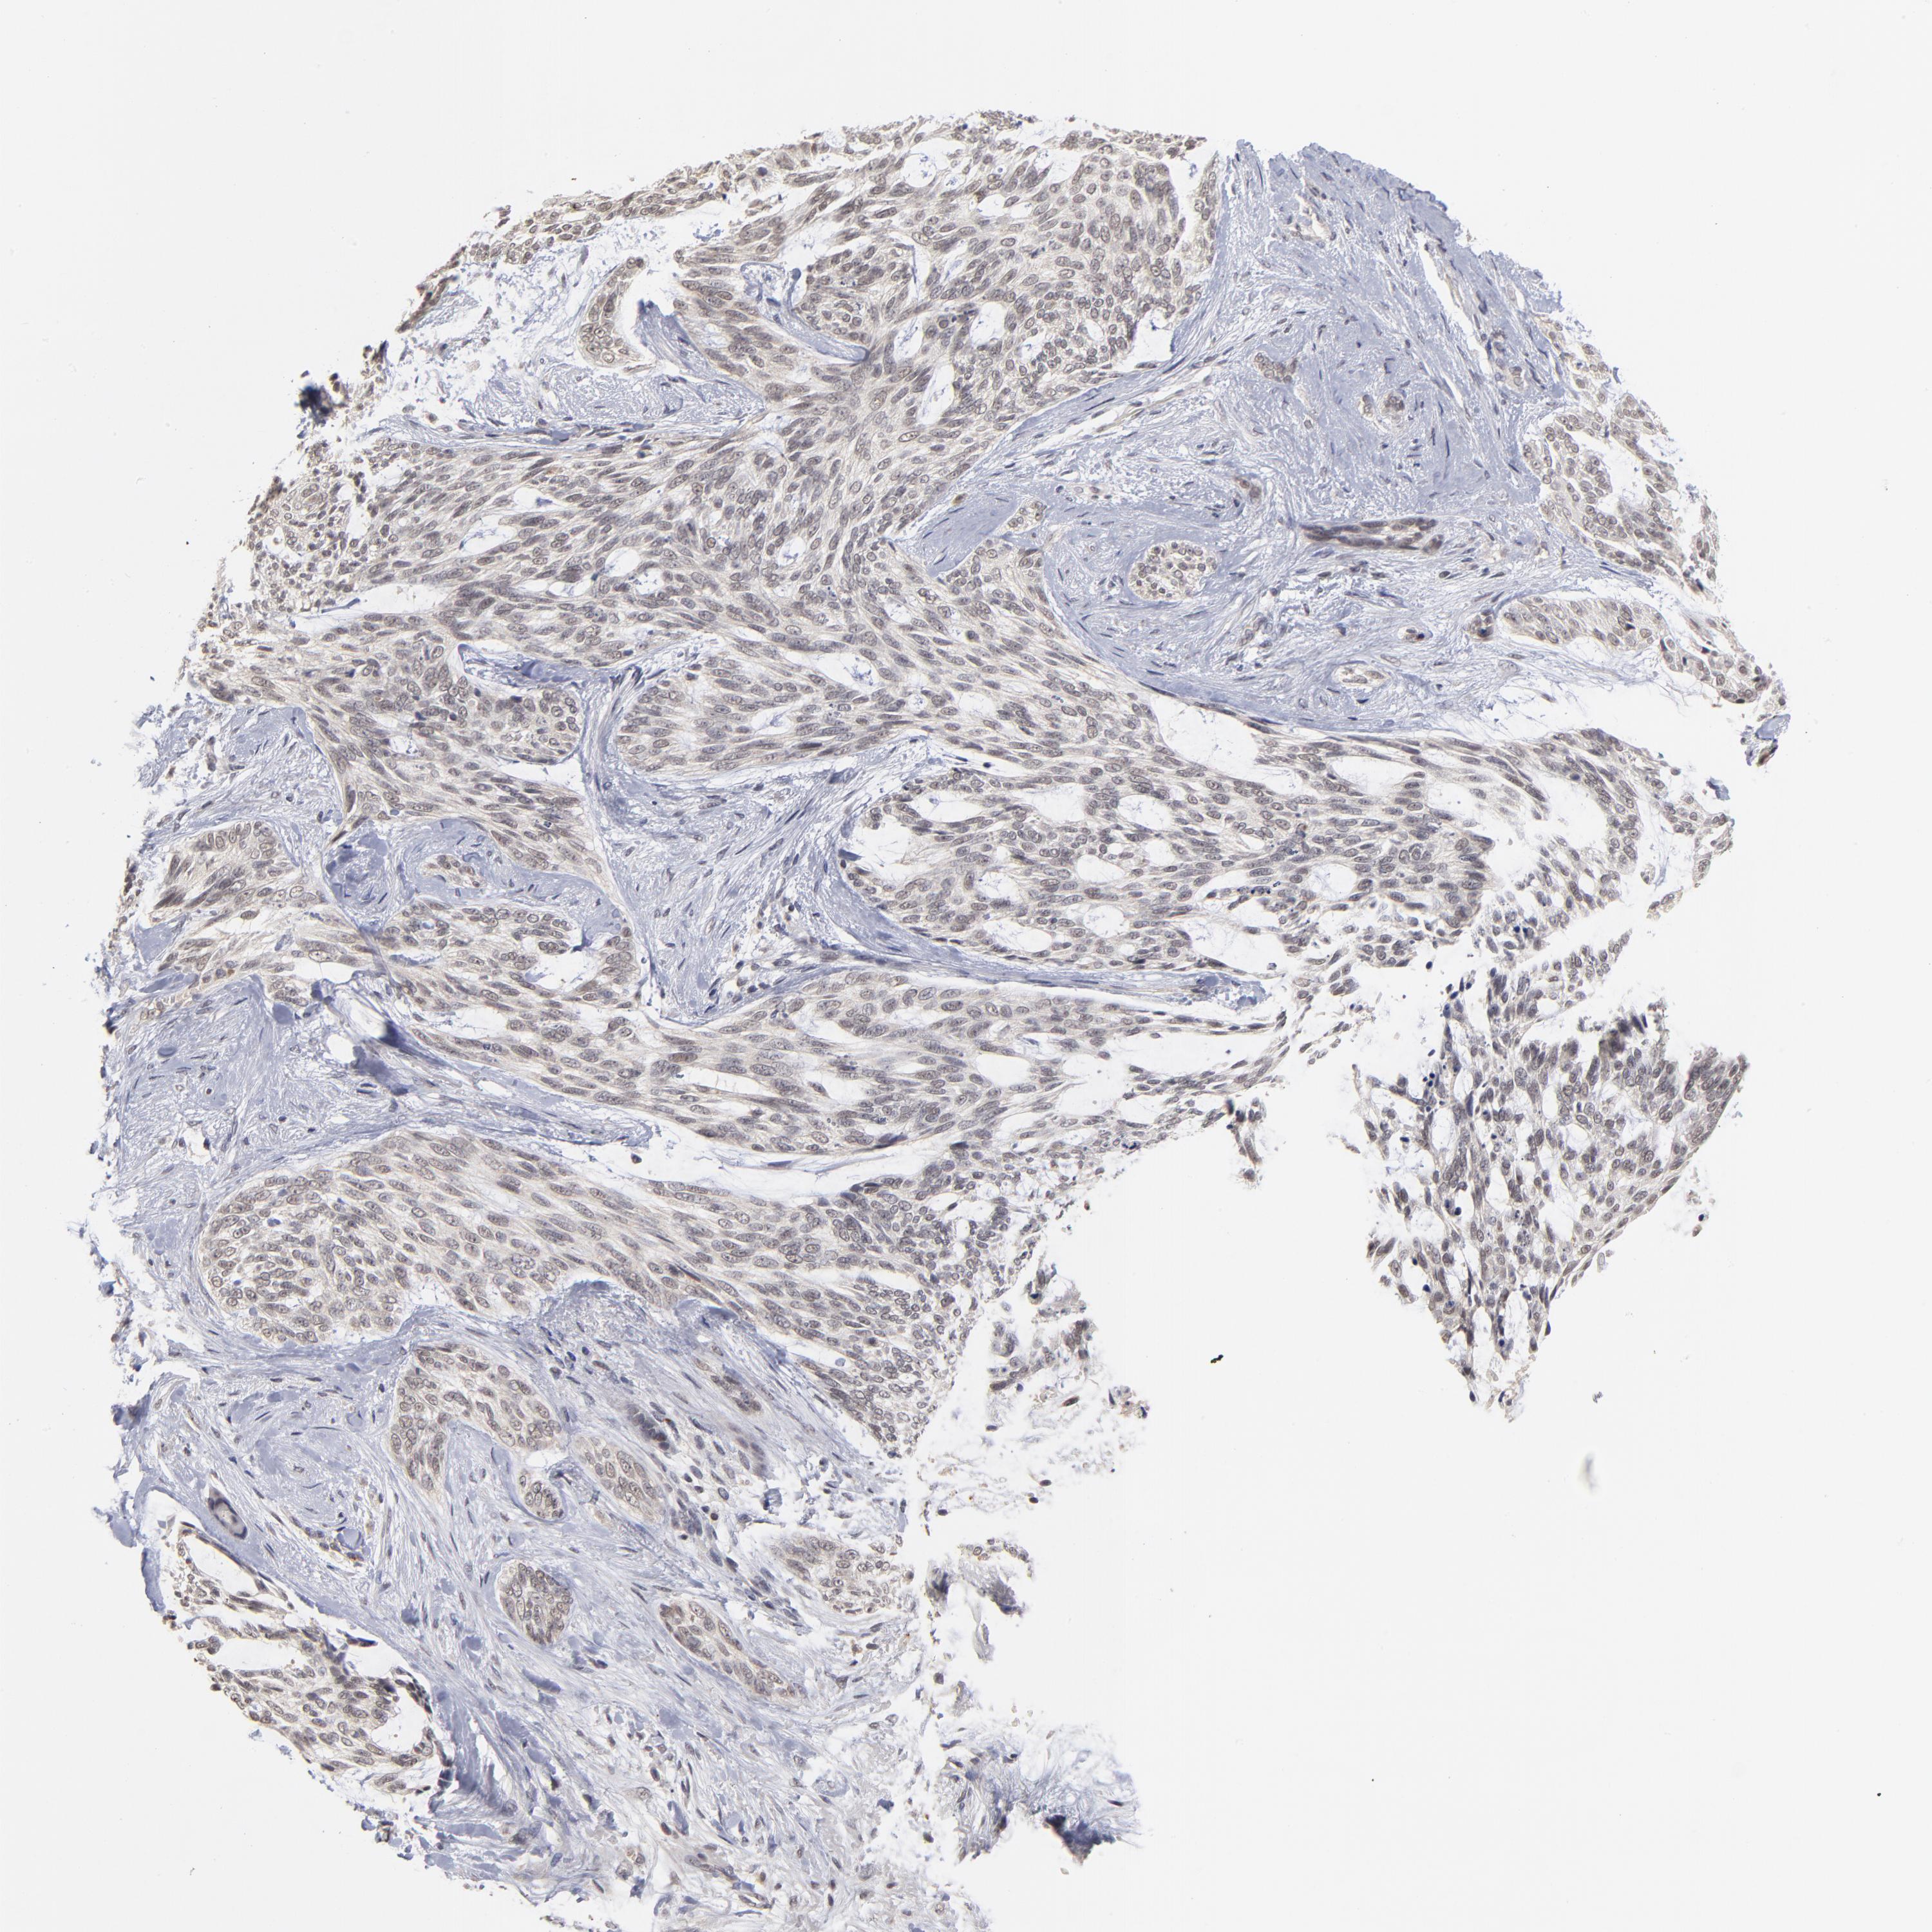

SKIN CANCER - Protein expressioni

A mouse-over function shows sample information and annotation data. Click on an image to view it in a full screen mode. Samples can be filtered based on level of antibody staining by selecting one or several of the following categories: high, medium, low and not detected. The assay and annotation is described here.

Antibody stainingi

Antibody staining in the annotated cell types in the current human tissue is reported as not detected, low, medium, or high, based on conventional immunohistochemistry profiling in selected tissues. This score is based on the combination of the staining intensity and fraction of stained cells.

Each image is clickable and will lead to virtual microscopy that enables deeper exploration of all samples and also displays staining intensity scores, fraction scores and subcellular localization as well as patient and tissue information for each sample.

Antibody HPA003293

Staining

High

Medium

Low

Not detected

Intensity

Strong

Moderate

Weak

Negative

Quantity

>75%

75%-25%

<25%

None

Location

Nuclear

Cytoplasmic/membranous

Cytoplasmic/membranous,nuclear

Squamous cell carcinoma, NOS

Basal cell carcinoma